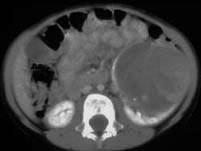

问题 女,54岁,发现腹部包块,请根据所示图像,选择最可能诊断 ( )

选项 A、左侧囊性肾癌 B、左侧肾血管平滑肌脂肪瘤 C、左侧单纯性肾囊肿 D、左侧肾囊肿合并出血 E、左侧肾癌

答案 A